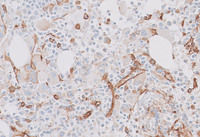

Figure 3: CD34 immunostain in CML–accelerated phase

Multiple images demonstrating several areas with increased numbers of CD34 positive blastic cells.  The cells reached up to 10% in some areas.  Occasional megakaryocytes demonstrate weak abnormal staining for CD34 noted on the image in the right.